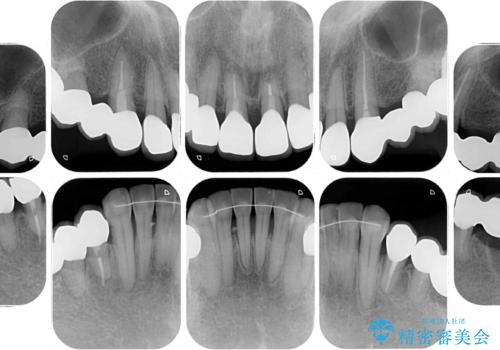

- 歯茎からの出血、入れ歯、歯の欠損、デコボコの前歯などを気にして来院された患者様です。

大の歯科治療嫌いとのことでしたが、今回の治療を契機にしっかりと治療を行いたいとのことでした。

まずは抜歯が必要な歯を抜歯した上で仮歯に置き換え、インプラント埋入や歯周外科処置、根管治療を行うこととしました。

歯肉の状態が落ち着いた後に下顎の矯正治療を行い、その後補綴治療を行うこととしました。